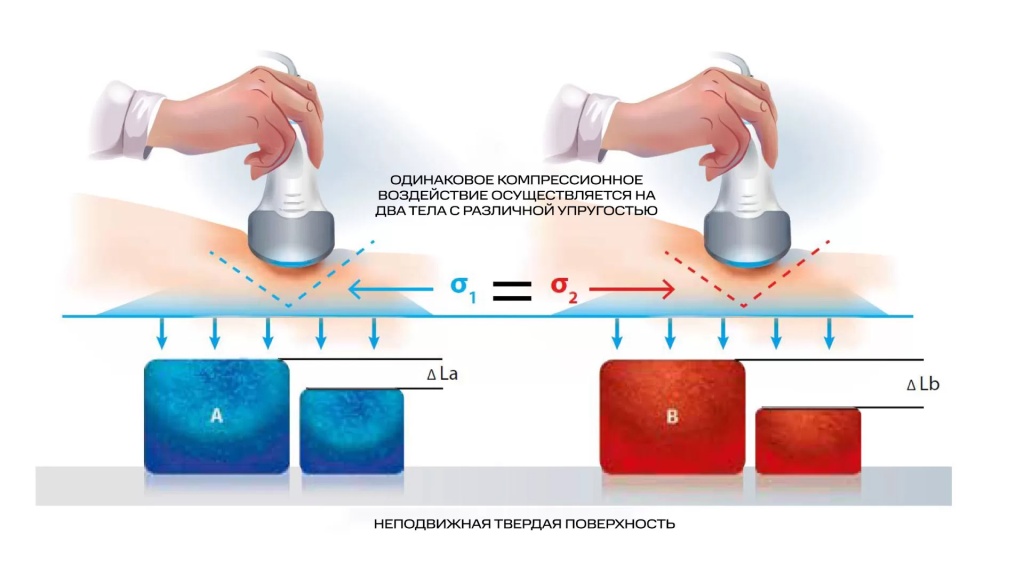

В начале обсудим методику стрейновой эластографии. Она основана на сравнительной оценке деформации (или стрейнов) тканей в области интереса. Деформация может вызываться как приложенной мануальной компрессией, когда мы датчиком слегка надавливаем на подлежащие структуры, так и физиологическими явлениями – передаточной пульсацией сердца, сосудов, дыхательными движениями, а в некоторых случаях и усиленным акустическим импульсом.

В данном случае получение абсолютных значений модуля Юнга (характеризующего жесткость тканей) невозможно, так как его значения зависят от приложенной силы, величина которой не стандартизирована и неизвестна. Поэтому проводится сравнение величины деформации, или стрейна. При воздействии одинаковой силы менее деформируемые ткани являются более жесткими, а более деформируемые – менее жесткими. Ультразвуковой сканер, работающий в специальном режиме, позволяет оценить и сравнить величину деформации тканей в окне опроса и картировать их соответствующим цветом, а также провести полуколичественную оценку – определить отношение деформации в зоне интереса и референсной (условно здоровой) ткани – StrainRatio.